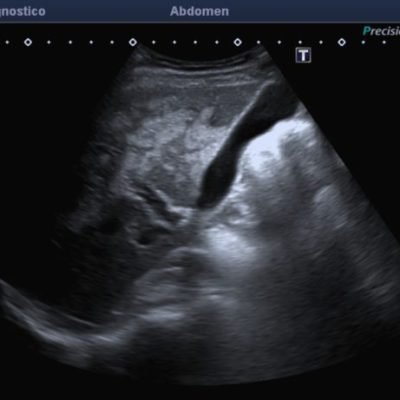

El médico de referencia le indica nueva ecografía de control, donde se observan múltiples y extensas lesiones focales hepáticas hiperecogénicas, redondeadas y confluentes, las cuales predominan en adyacencia a venas supra hepáticas, sin condicionar efecto de masa y sin alteración de la superficie hepática(fig. 1 y 2). Ante la valoración con Doppler color no presenta patrón de flujo peri ni intralesional y respeta el calibre de las venas supra hepáticas(fig. 3 y 4). Dada las características ecográficas se sospecha esteatosis focal multinodular confluente como principal diagnóstico presuntivo, siendo los diagnósticos diferenciales patologías de naturaleza infecciosa, tumoral o metastásica.